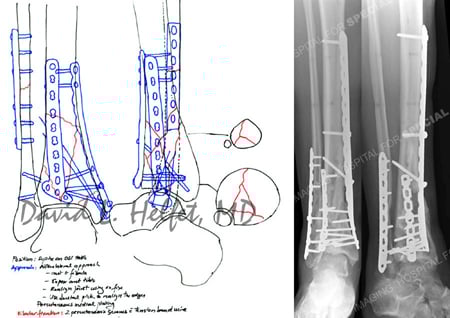

Pre-operative plan for open reduction and internal fixation

(1 week following placement of a spanning external fixator and fibula plating).